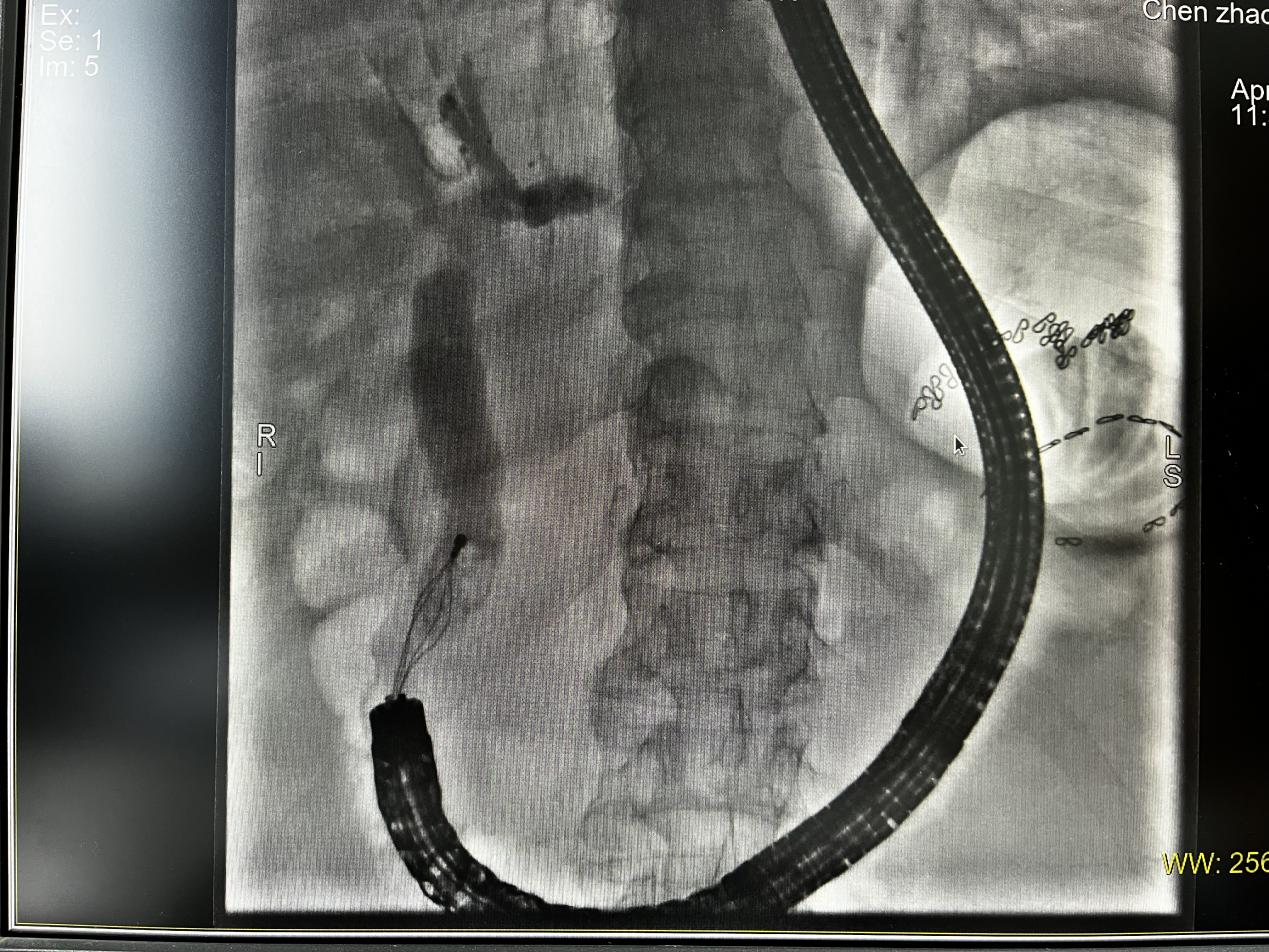

术中,消化内科团队凭借丰富的经验,在肠镜引导下巧妙调整进镜角度,成功定位乳头并完成插管,最终顺利取出胆总管结石。手术全程患者生命体征平稳,未出现出血、穿孔等并发症。患者住院6天,症状完全缓解,目前已康复出院。

X线下网篮取石